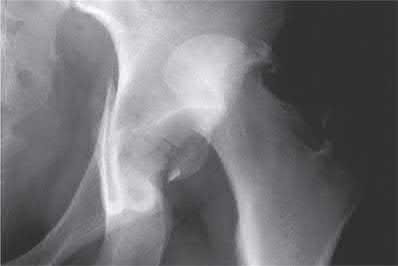

A 13-year-old obese boy presents with non-traumatic knee pain and is noted to have an obligate external rotation of his hip when it is passively flexed. Radiographs confirm the diagnosis. He is unable to bear weight on the affected extremity. What is the primary complication associated with this presentation compared to a patient who is able to bear weight?

Options:

Correct Answer: Avascular necrosis (AVN) of the femoral head

Explanation:

The patient has an unstable slipped capital femoral epiphysis (SCFE), defined by Loder criteria as the inability to bear weight even with crutches. Unstable SCFE has a significantly higher rate of avascular necrosis (up to nearly 50% in some series) compared to stable SCFE (which has an AVN rate near 0%). Both stable and unstable SCFEs can lead to impingement or contralateral slips, but AVN is the critical distinguishing risk factor of an unstable slip.